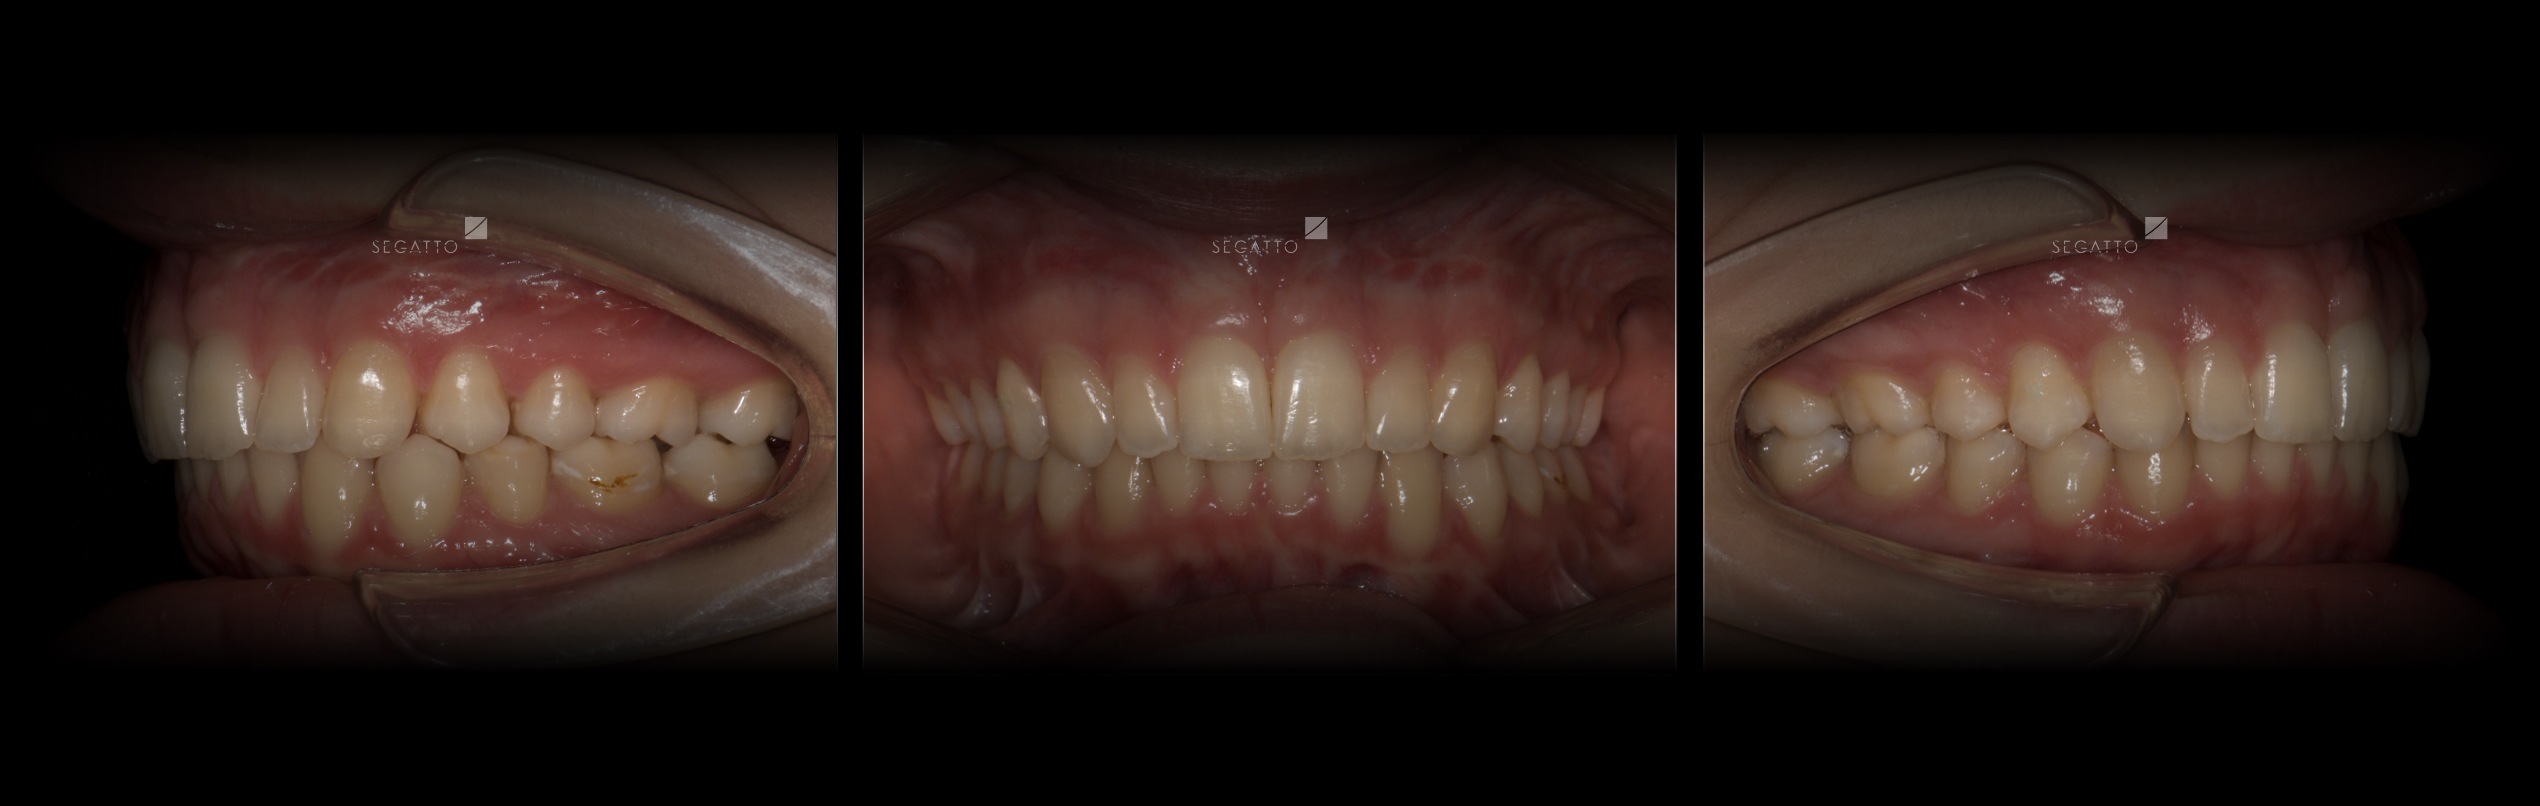

Orthodontics

Cases